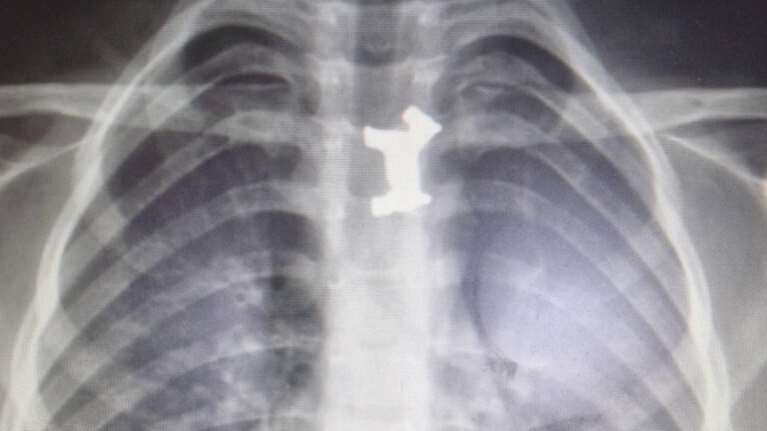

Αγοράκι κατάπιε μεταλλικό σκυλάκι - Σωτήρια επέμβαση στο Ιπποκράτειο

Γιατροί του Ιπποκρατείου Νοσοκομείου κατάφεραν να αφαιρέσουν με επιτυχία ένα μεταλλικό σκυλάκι από τον οισοφάγο ενός αγοριού 4,5 ετών από τις Σέρρες.